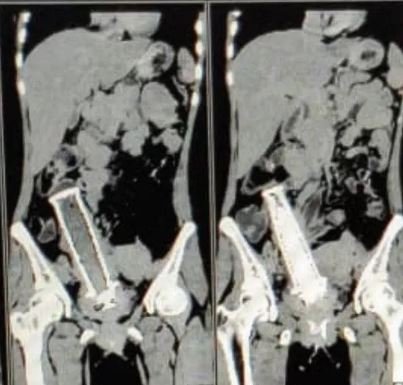

Με το στόμα ανοιχτό έμειναν οι γιατροί στο νοσοκομείο ΜΥ του Ιντόρε της Ινδίας, με τα όσα αντίκρισαν στην ακτινογραφία μίας γυναίκας.

Η 30χρονη είχε φτάσει εκεί με μεγάλους πόνους στο στομάχι και έτσι αποφασίστηκε να της κάνουν εξετάσεις, προκειμένου να διαπιστωθεί τι πήγαινε στραβά.

Αυτές λοιπόν, σύμφωνα με το Cover Asia Press, έδειξαν πως όλα ήταν αποτέλεσμα της ύπαρξης μίας χειρολαβής από μηχανάκι στην μήτρα της!

«Μας είπε πως την χειρολαβή την έβαλε μέσα της, ο άνδρας της, όταν μία μέρα είχε γυρίσει σπίτι μεθυσμένος.

Την είχε απειλήσει μάλιστα να μην το πει σε κανέναν γιατί θα την χτυπούσε.

Το συγκεκριμένο αντικείμενο ήταν μέσα της για περίπου δύο χρόνια, με αποτέλεσμα να δημιουργήσει μολύνσεις.